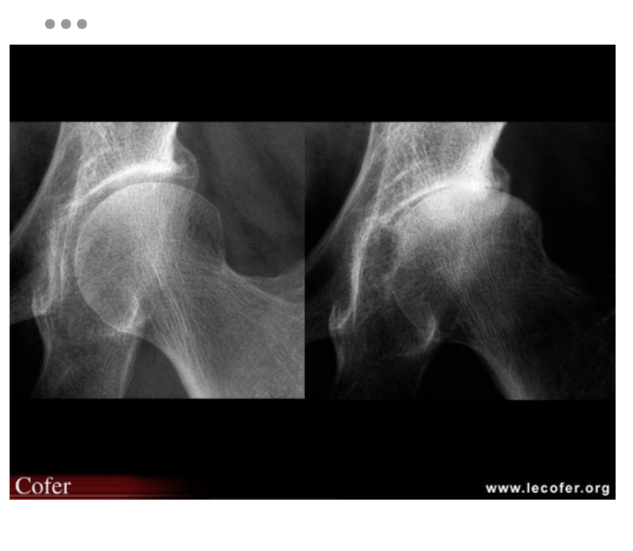

Coxarthrose bilatérale

pincement supéro-externe de l’interligne coxo-fémorale bilatérale

Coxarthrose destructrice rapide

pincement supéro-externe de l’interligne coxo-fémorale